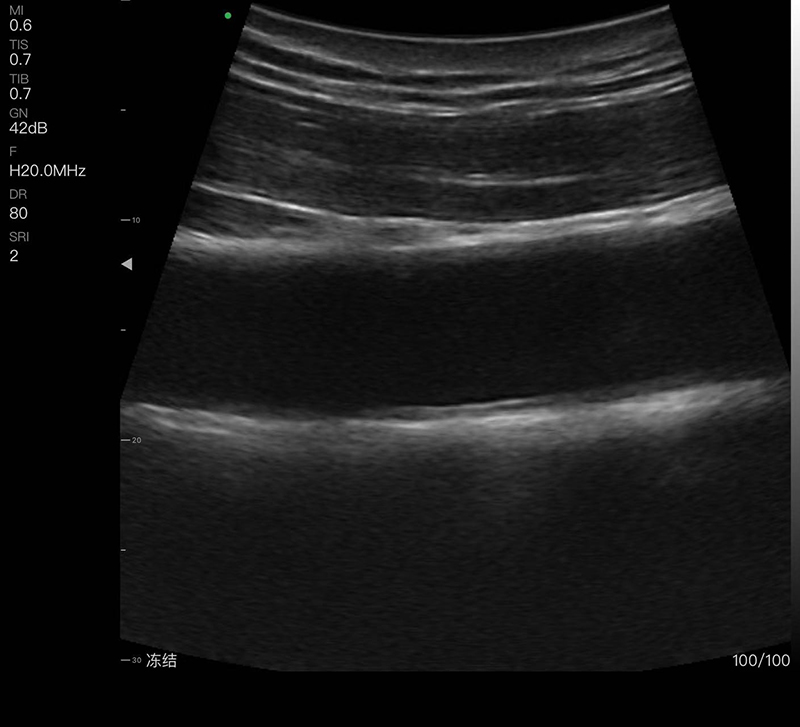

带指套探头的掌上彩超,小小的掌超主机放在口袋可随处走,手指套着探头即可完成打图成像,让手不再需要握着探头而可解放出来还能拿其他东西,特别适合术中等应用

- 探头频率:16/20MHz

- 扫描深度:10/20/30/40mm,可调

- 显示模式:B、B/M、COLOR、PDI、PW